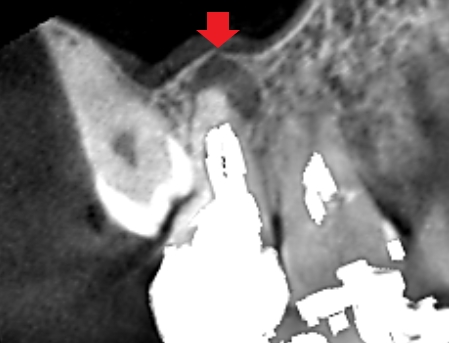

上顎第二大臼歯の冠状断のCT画像です。

赤い矢印の先に膿の影がみられます。